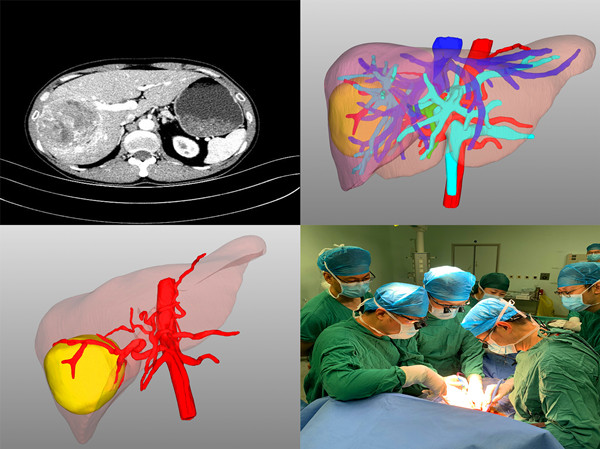

患者2,男,44岁,诊断“原发性肝癌”。术前评估:全身评估及营养评估未见异常;肝功能Child-Pugh-Turcotte分级A级,ICGR15 0.6%;病灶及可切除性评估:肿瘤位于肝脏V-VIII段,约8*7.5*7.5cm大小,侵犯肝右静脉中远端及相应肝段Glisson系统;门静脉无变异(A型),右肝动脉发自肠系膜上动脉,裂静脉与肝中静脉根部共干;肝内胆管无扩张;拟行解剖性右半肝切除术,患者总肝体积1877.27ml,标准肝体积1191.08mL,右半肝体积1126.23mL,左半肝体积为751.04,Rsr为63.1%,结合当前患者肝功能及ICGR15水平,Rse为40% 患者3,男,36岁,诉“发现胰体尾占位1周”,术前诊断“胰体尾实性假乳头状瘤”。患者因颈椎病,在骨科住院查出胰腺占位性病变,转入我科治疗,术前评估:全身评估及营养评估未见异常;肝肾功正常:肿瘤位于胰尾部近脾门处,经三维重建后,可见脾动脉及脾静脉分两支型,紧紧包绕肿块,决定腹腔镜下行胰体尾联合脾脏切除。术中探查见上脾门区致密粘连,给手术来带了一定的困难和挑战。凭借术中三维精准导航和精细的手术解剖,胰体尾及脾脏被顺利切除。手术历时2.0h,术中出血约50mL,目前患者恢复良好,拟于近日出院。 术后在谈及专业划分后一周的肝胆胰外科工作时,陆宏伟教授表示,肝胆胰外科手术操作犹如荒野探险,术前永远无法完全把握未知的前方有哪些解剖变异和挑战等待着你,因此只能通过术前精准的治疗规划、术中结合影像学进行精细的外科操作和术后精心的个体化管理,使患者最大程度的获益。 陆宏伟教授师从于我国著名肝胆胰外科专家董家鸿院士,对于肝胆胰良恶性肿瘤和胆管扩张症的精准诊疗及肝脏移植术具有丰富经验。目前陆宏伟教授团队已与北京清华长庚医院董家鸿院士团队、中国人民解放军总医院段伟东教授团队建立长期临床及科研合作关系,这将进一步提升团队的肝胆胰疾病诊断和外科治疗水平。